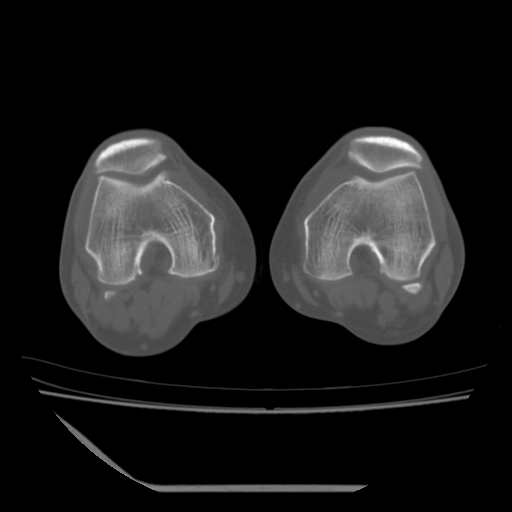

标题: CT13225:老年男性,左膝关节疼痛数月;请各位老师讨论。 [打印本页]

标题: CT13225:老年男性,左膝关节疼痛数月;请各位老师讨论。

骨质增生,骨性关节面硬化,关节积液,考虑退行性骨关节病

关节腔内少量积液,关节面退变。

双膝退变

骨质增生,骨性关节面硬化,关节间隙失常,关节积液,考虑退行性骨关节病.

这个病例诊断:退行性骨关节炎